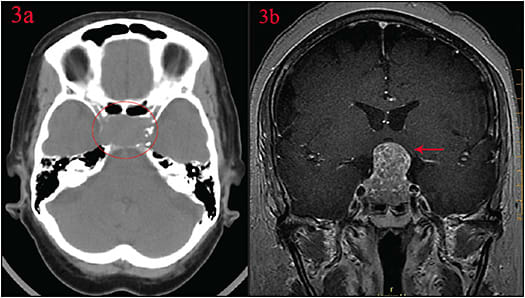

Considering her visual field deficits, IOP in the low teens and previously noted optic nerve thinning on GDx despite minimal optic nerve cupping on exam, we had to consider the possibility of intracranial pathology in this patient. Computed tomography (CT) and magnetic resonance imaging (MRI) were ordered to rule out lesions at the optic chiasm.

CT head and MRI brain studies were significant for 2.1 x 2.7 cm pituitary mass with suprasellar extension consistent with pituitary adenoma (Figures 3A and 3B).